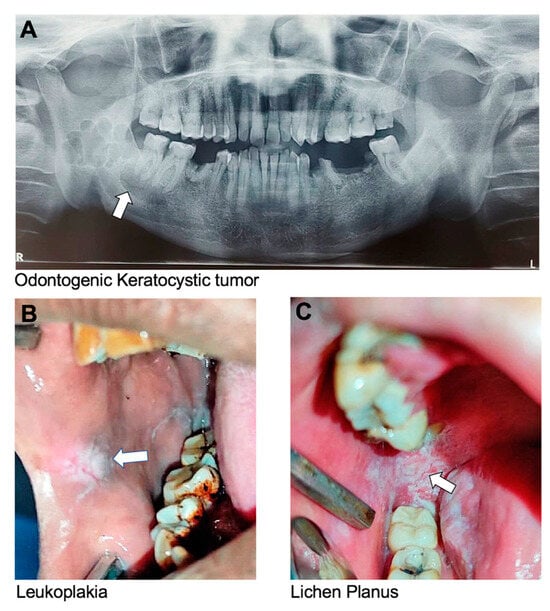

Figure 2. Oral conditions with strong genetic components as per our data analysis of retrieved articles. (A) Panoramic radiograph image of individual with oligodontia showing absence of six permanent teeth (excluding third molars). The following teeth are missing: 12, 15, 22, 25, 35, and 45, using the FDI numbering system (courtesy of Dr. Ariadne Letra). (B) Panoramic radiograph image of individual with impacted third molars. (C) Amelogenesis imperfecta showing enamel pitting with exposed dentin (courtesy of Dr. Cleverick (C.D.) Johnson). (D) Supernumerary teeth. (E) Mandibular micrognathia showing short lower jaw. (F,G) Dentigerous cyst (Image G is courtesy of Dr. Ritu Tiwari). (H) Ameloblastic fibroma at the lower left quadrant.

Oligodontia is a rare genetic condition that affects the development of teeth during childhood, characterized by six or more missing permanent teeth (Figure 2A), and is similar to hypodontia. Oligodontia can be caused by mutations in various genes involved in tooth development, like AXIN2, MSX1, and PAX9 [11,12,13,14,16,20,21,22,23]. MSX1 mutations impair the initial stages of dental development, while PAX9 mutations affect epithelial–mesenchymal interactions necessary for early tooth formation [12,19]. The condition can also be associated with other congenital syndromes, such as ectodermal dysplasia, Down syndrome, or familial cleft lip and palate, which are inherited in an autosomal-dominant pattern [20,21,22,23].

Impacted teeth are teeth that cannot emerge fully into the mouth due to a lack of space, an obstruction in their eruption path, and/or a misalignment resulting in a lack of an eruptive path; all these factors are influenced by genetics (Figure 2B). This can occur with any tooth in the mouth, but it most commonly affects the third molars, or wisdom teeth, and maxillary canines [44,45].

Amelogenesis imperfecta (AI) is a genetic disorder that affects the development of tooth enamel, which is the hard, protective, outer layer of teeth. This condition can affect both primary and permanent teeth, and it can result in teeth that are discolored, weak, and prone to fracture [46]. There are several types of AI, each with its own specific pattern of inheritance and symptoms. The disorder can be inherited in an autosomal-dominant, autosomal-recessive, or X-linked manner, depending on the specific genetic mutation involved [28]. Mutations in the genes AMELX, ENAM, MMP20, KLK4, and DLX3 are reported to be associated with the development of AI [9,28,46,47]. Clinically, teeth affected by AI may be yellow or brown, have rough or pitted surfaces, or be abnormally small or misshapen (Figure 2C). Teeth affected by this condition may also be sensitive to temperature and pressure.

3.1.6. Supernumerary Teeth

Micrognathia is a congenital medical condition characterized by an abnormally small mandible or maxilla (Figure 2E). Micrognathia can be caused by various factors, including genetic abnormalities, or problems with the growth and development of the jaw bones during fetal development [62]. It can also occur due to environmental factors, such as exposure to certain medications or toxins during pregnancy [62]. Mutations in more than fifteen different groups of genes have been associated with the development of micrognathia [62]. Micrognathia can occur in isolation or as part of a symptom of other craniofacial conditions. For example, micrognathia is often seen as part of the Pierre Robin sequence that is mostly caused by mutations in SOX9 [62,63]. The Pierre Robin sequence occurs in about 1 per 8500 live births [64]. It is called a sequence due to a sequence of events that occur during fetal development—the mandible does not grow enough, which causes the tongue to be pushed back, preventing the secondary palatal shelves from developing, leading to a failure of the palatal bones to close and remain separated in the midline. Babies born with the Pierre Robin sequence may have difficulty breathing, feeding, and/or sleeping. Symptoms can range from being very mild to quite severe, including an underdeveloped mandible, cleft palate, glossoptosis, and airway obstruction [64].

Dentigerous Cyst

Ameloblastic Fibroma

Keratocystic Odontogenic Tumor (KCOT):